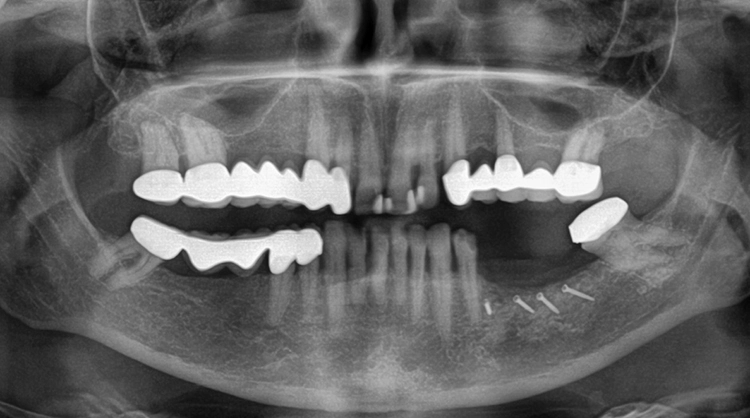

Eine 63-jährige Patientin stellte sich mit einer schon seit längerer Zeit bestehenden Schaltlücke im Unterkiefer links vor. Ziel der geplanten Behandlung war die adäquate prothetische Neuversorgung mittels einer implantatgetragenen Brücke (Abb. 1).

Der Prämolar 35 wies einen hohen Lockerungsgrad und Knochenabbau auf und musste daher extrahiert werden (Abb. 2). Nach einer Ausheilungsphase von sechs Wochen erfolgte die Rekonstruktion des verlorengegangenen Knochens (Abb. 3 und 4). Es erfolgte die Knochenentnahme retromolar und die Schalen wurden in der Folge mit Hilfe des sog. Safescrapers (Firma Meta) weiter ausgedünnt. Nun erfolgte die Rekonstruktion des Knochendefekts, wobei die zuvor entnommenen Knochenschalen (Split Bone Technik nach Prof. Khoury) bukkal auf Distanz gesetzt und mit kleinen Osteosyntheseschrauben fixiert wurden.